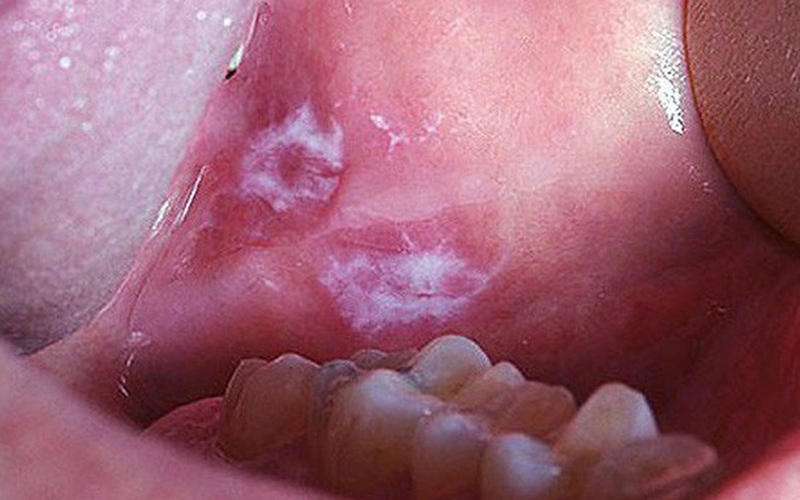

Lichen phẳng và cách chữa nhanh để ngăn ngừa nguy cơ ung thư miệngHình ảnh chụp lichen phẳng trong khoang miệng

• Xuất hiện những mảng trắng hoặc vết loét trong khoang miệng, khiến cho vùng mô xung quanh sưng tấy đỏ. Những vết này thoạt nhìn như những vết bỏng gây sưng đau rất khó chịu.

• Những vết sưng trong khoang miệng có thể phân bố thành những nhóm cụm với hình oval, hình tròn và rải rác trên vòm miệng.

• Sau vài ngày thì những vết loét co cụm lại với nhau giống như hình dạng đồ thêu ren với những mảng bông trắng.